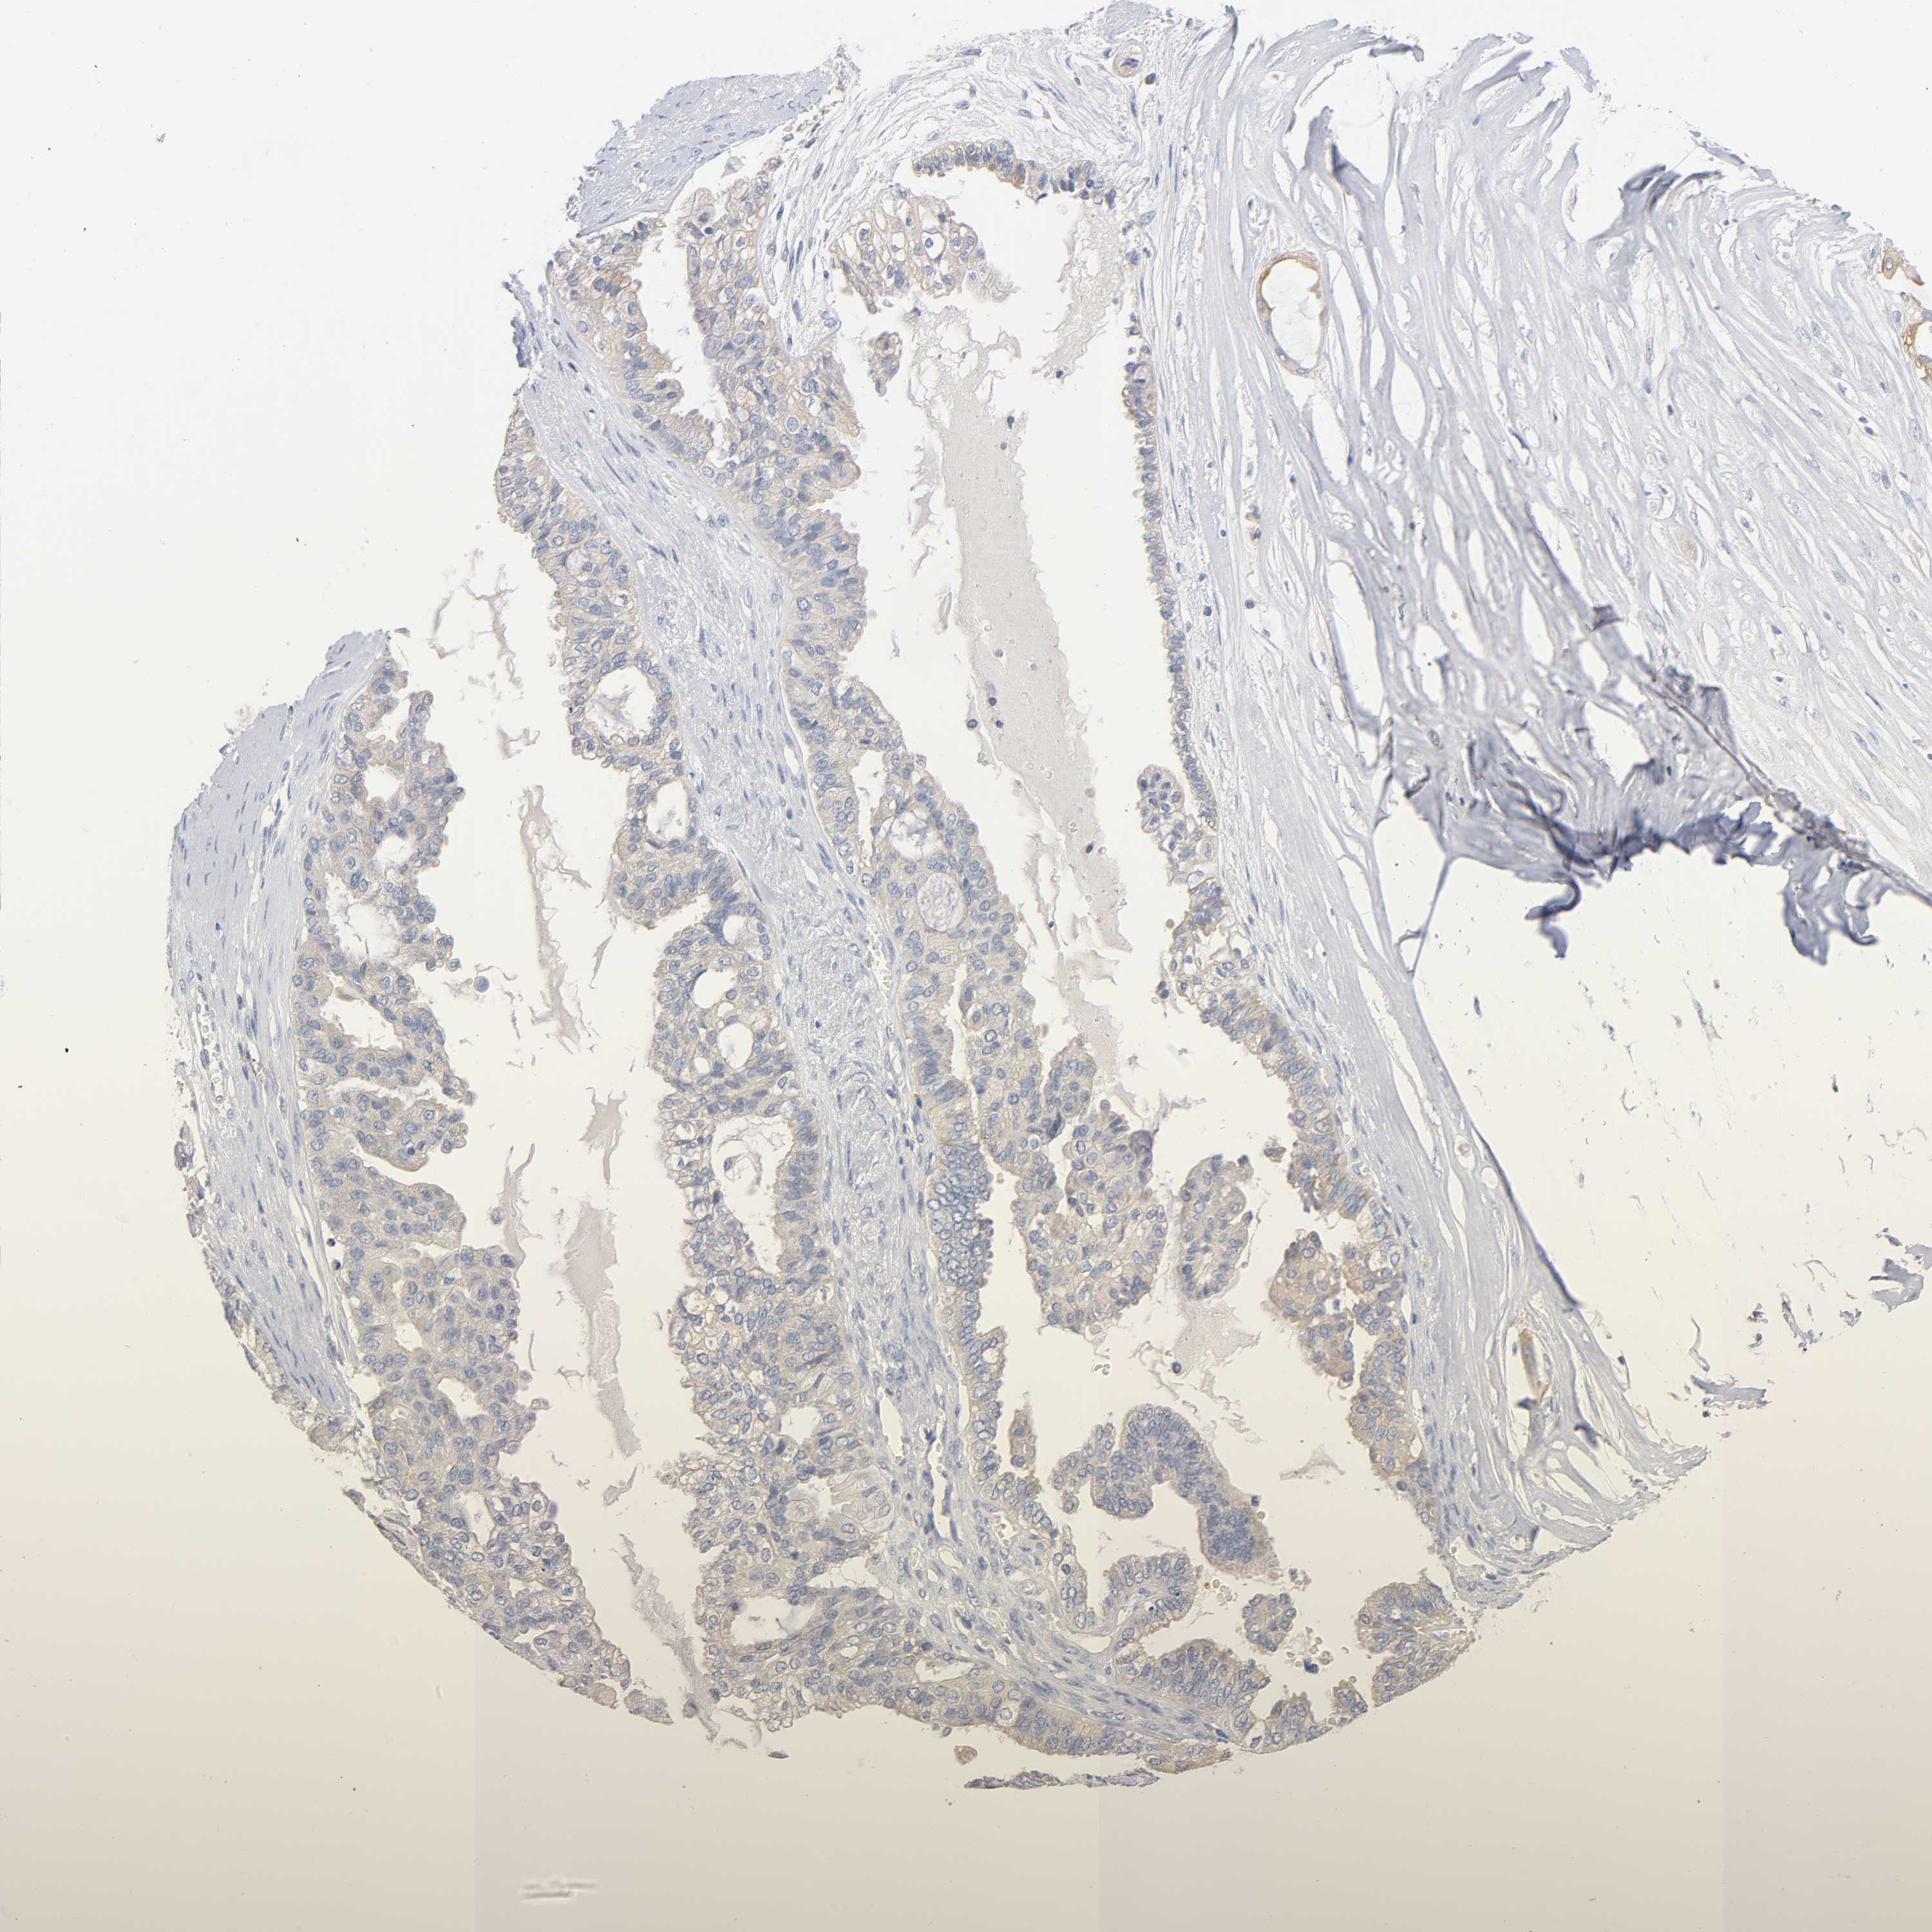

OVARIAN CANCER - Protein expressioni

A mouse-over function shows sample information and annotation data. Click on an image to view it in a full screen mode. Samples can be filtered based on level of antibody staining by selecting one or several of the following categories: high, medium, low and not detected. The assay and annotation is described here.

Note that samples used for immunohistochemistry by the Human Protein Atlas do not correspond to samples in the TCGA dataset.

Antibody stainingi

Antibody staining in the annotated cell types in the current human tissue is reported as not detected, low, medium, or high, based on conventional immunohistochemistry profiling in selected tissues. This score is based on the combination of the staining intensity and fraction of stained cells.

Each image is clickable and will lead to virtual microscopy that enables deeper exploration of all samples and also displays staining intensity scores, fraction scores and subcellular localization as well as patient and tissue information for each sample.

Antibody CAB004494

Cystadenocarcinoma, serous, NOS

Carcinoma, endometroid

Carcinoma, NOS

Cystadenocarcinoma, mucinous, NOS